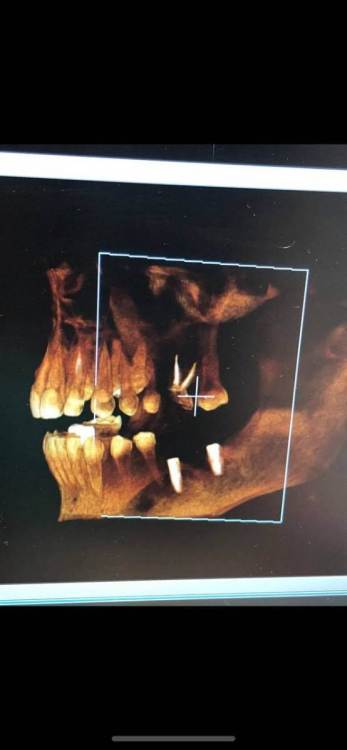

Здравствуйте ! Ситуация следующая - 6 сверху коронка с резекцией , долгое время осталась без антагониста , соотвественно выдвинулась (это уже мое предположение) . Чтобы спасти зуб , доктор принял решение повести гемисекцию корня . После - осталась рассечена десна .. Доктор говорит десна заживет , но визуал мягко говоря напрягает , так как при улыбке у меня это все видно ..

Фото 7,8 - Также была проведена резекция кисты 5 зуба снизу , с коронкой , и установка 7 импланта в качестве антагониста верхней 7 . Одной операцией . Коронка оголилась , швы сняли на 3 день .. доктор также утверждает что в дальнейшем будет все хорошо , зарастет . Также очень смешает внешний вид десны , десна стала волной даже на 6 ..